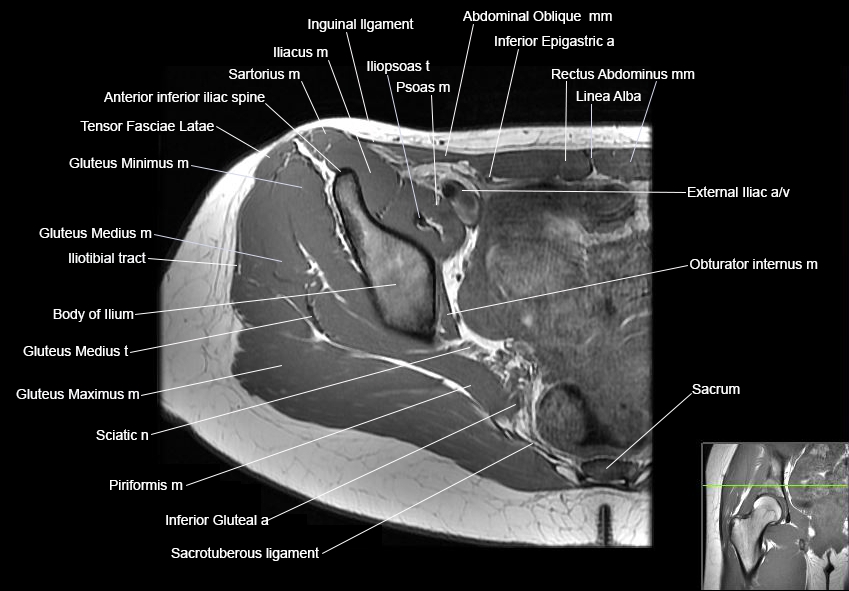

Hip

Basic Hip MRI

MRI Hip Anatomy

Scroll using the mouse wheel or the arrows